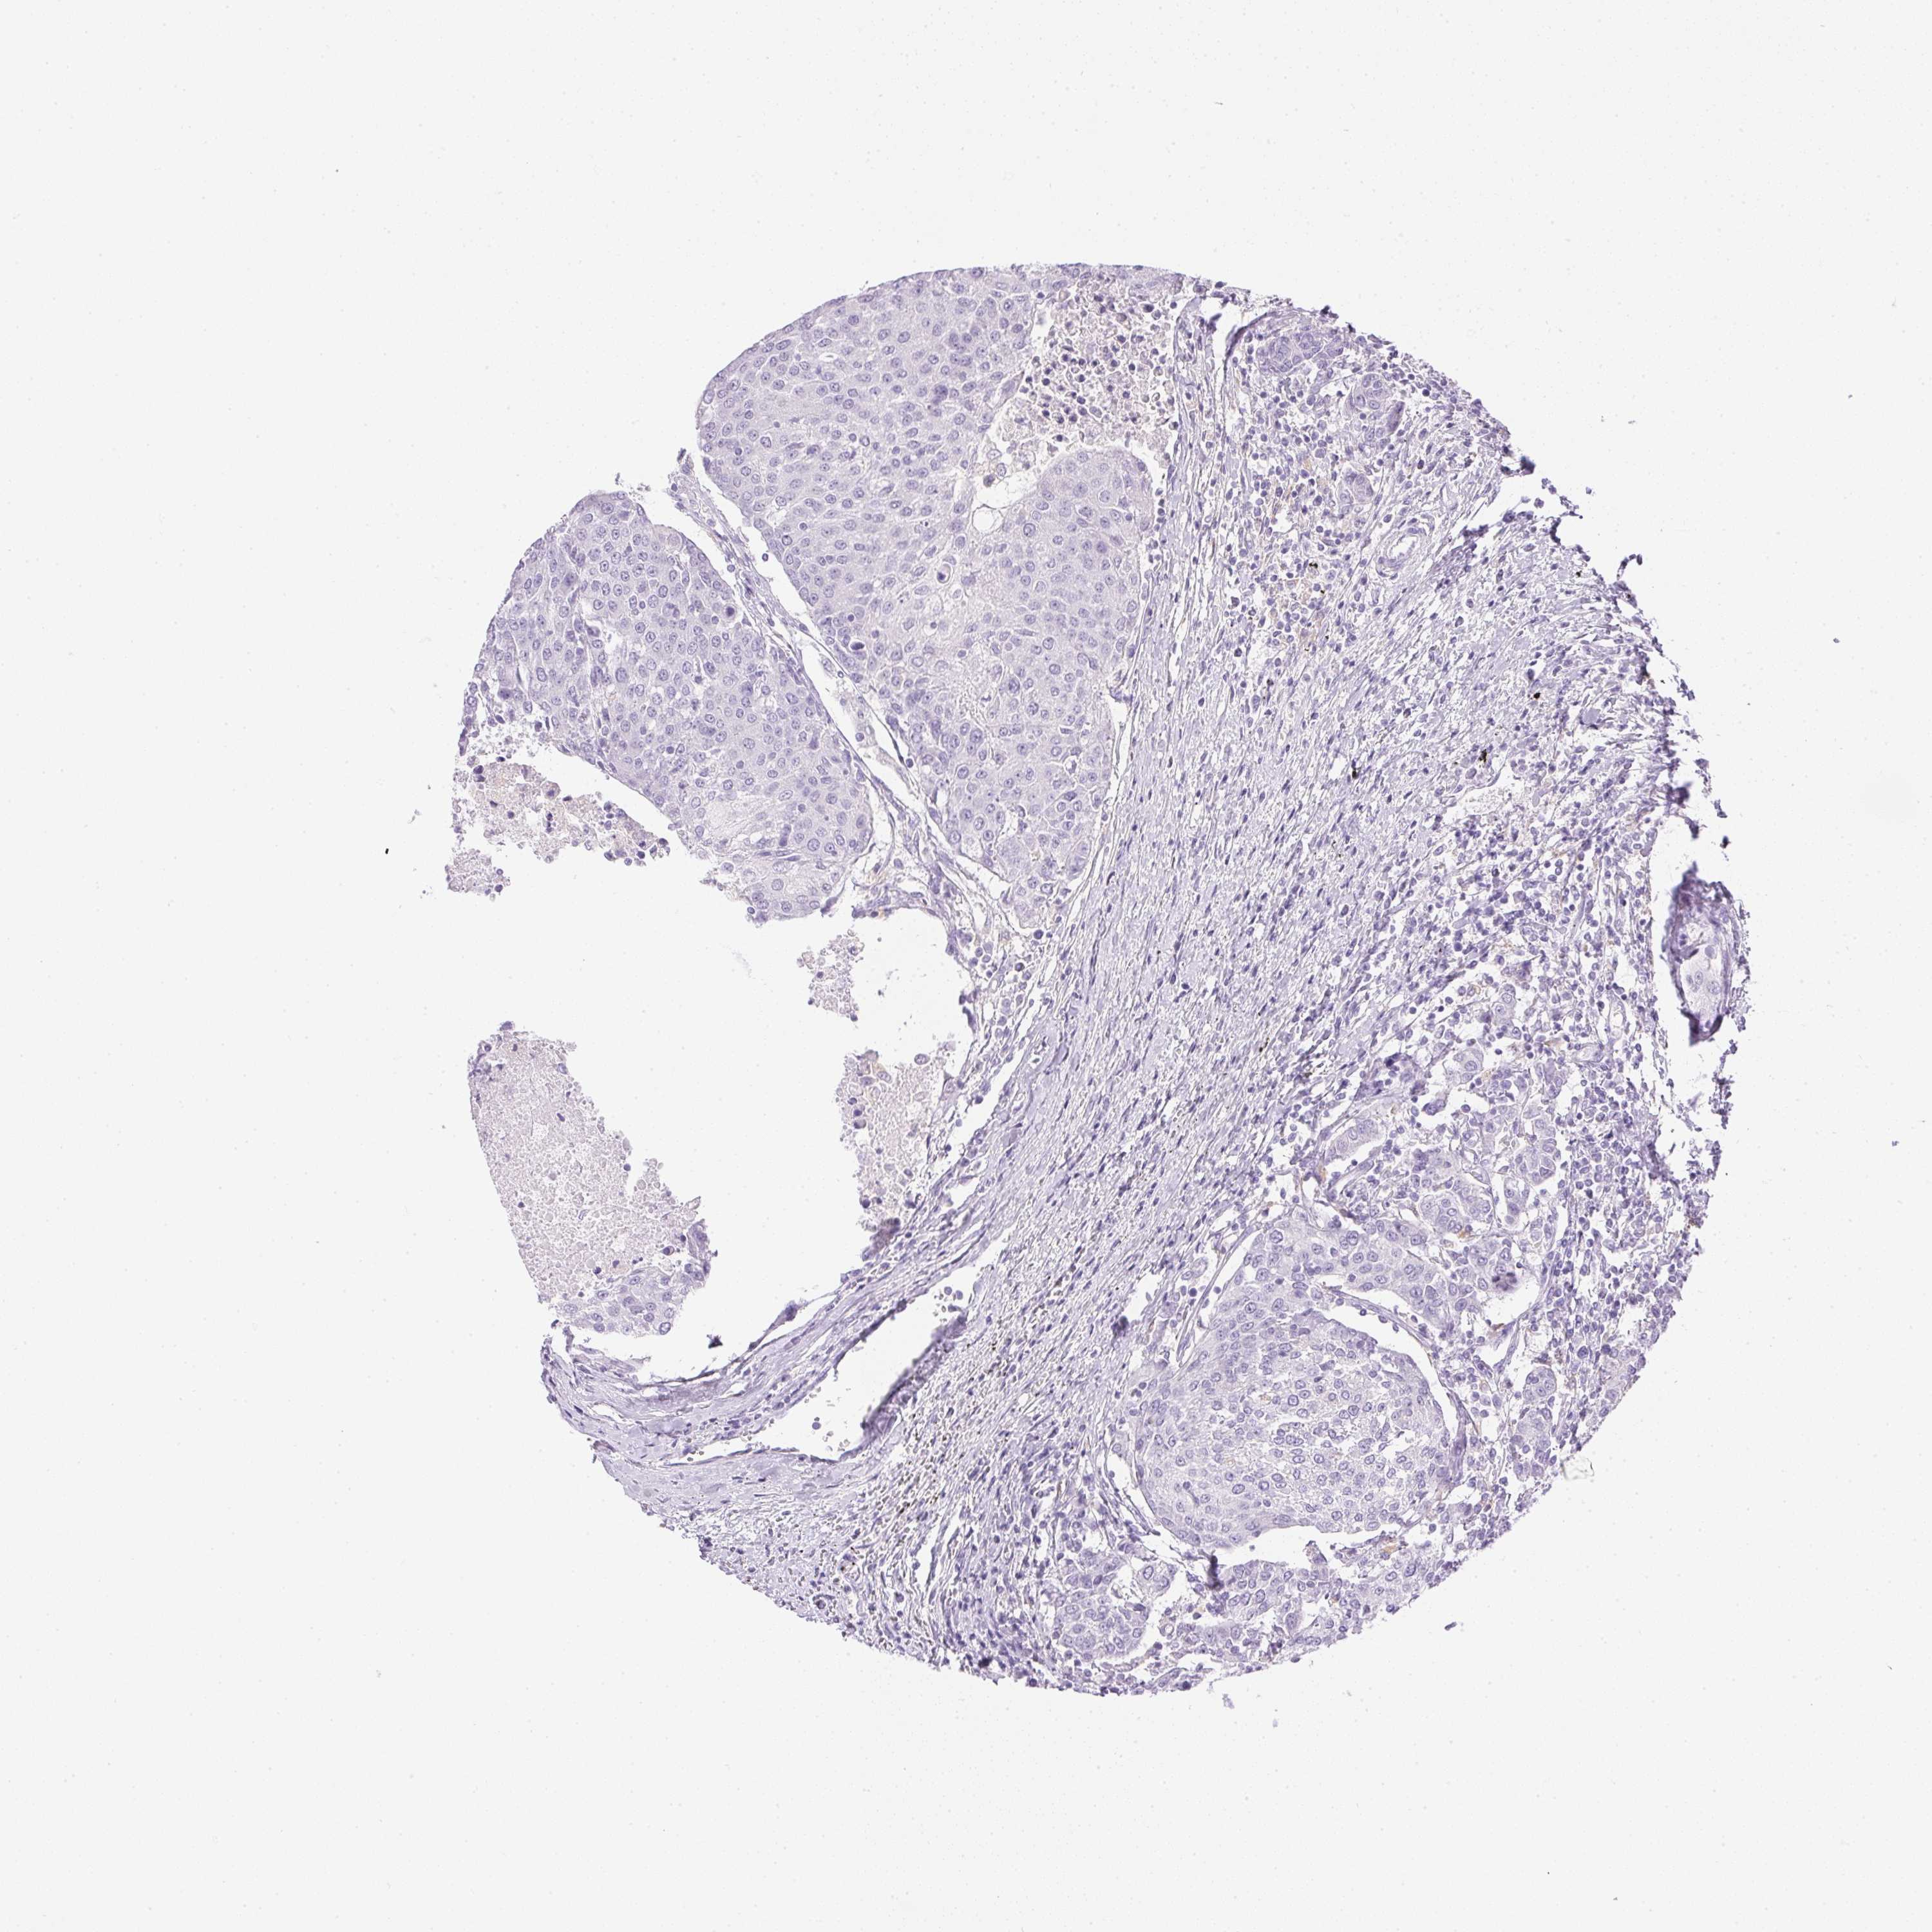

UROTHELIAL CANCER - Protein expressioni

A mouse-over function shows sample information and annotation data. Click on an image to view it in a full screen mode. Samples can be filtered based on level of antibody staining by selecting one or several of the following categories: high, medium, low and not detected. The assay and annotation is described here.

Note that samples used for immunohistochemistry by the Human Protein Atlas do not correspond to samples in the TCGA dataset.

Antibody stainingi

Antibody staining in the annotated cell types in the current human tissue is reported as not detected, low, medium, or high, based on conventional immunohistochemistry profiling in selected tissues. This score is based on the combination of the staining intensity and fraction of stained cells.

Each image is clickable and will lead to virtual microscopy that enables deeper exploration of all samples and also displays staining intensity scores, fraction scores and subcellular localization as well as patient and tissue information for each sample.

Antibody HPA028701

Staining

High

Medium

Low

Not detected

Intensity

Strong

Moderate

Weak

Negative

Quantity

>75%

75%-25%

<25%

None

Location

Nuclear

Cytoplasmic/membranous

Cytoplasmic/membranous,nuclear

Urothelial carcinoma, High grade

Urothelial carcinoma, Low grade

Urothelial carcinoma, NOS